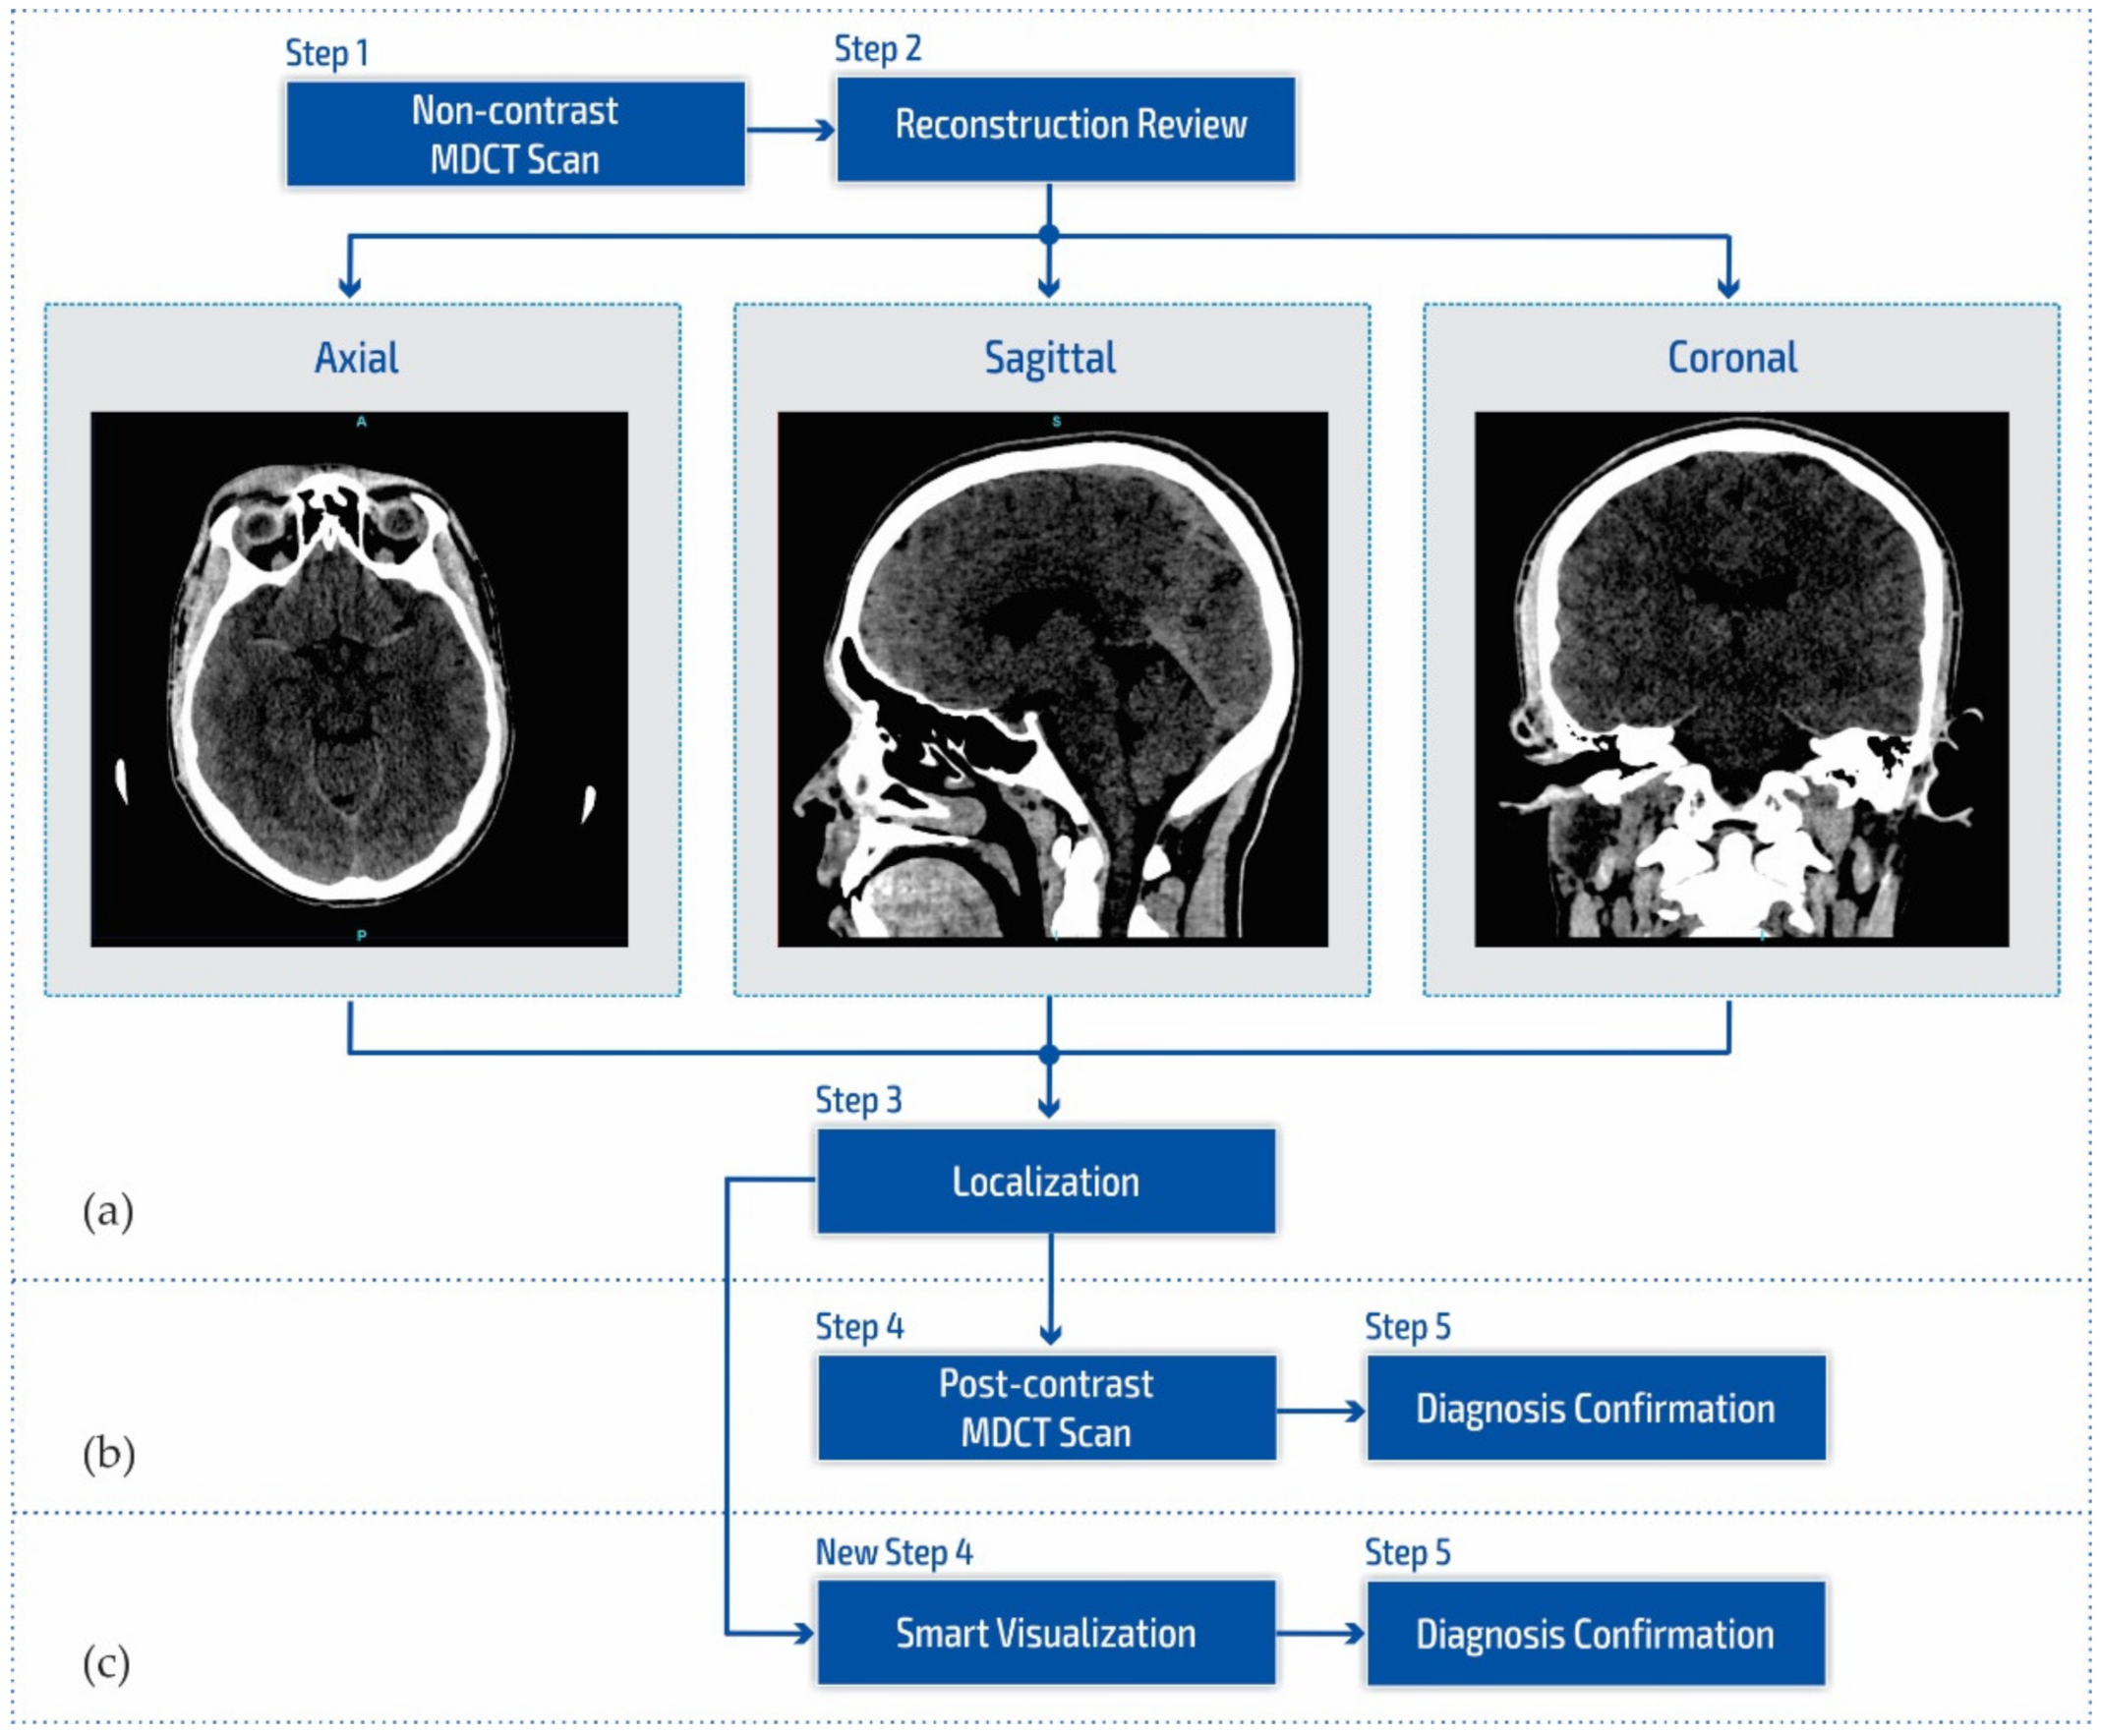

2. Materials and Methods

2.1. Standard Methods and Existing Problems

2.2. Smart Visualization Method (SVMI)

3.1. Technological Description